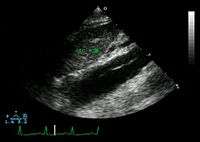

Transesophageal ultrasound

The transesophageal echocardiogram (TEE) is a relatively good test in the diagnosis of aortic dissection, with a sensitivity up to 98% and a specificity up to 97%. It has become the preferred imaging modality for suspected aortic dissection. It is a relatively noninvasive test, requiring the individual to swallow the echocardiography probe. It is especially good in the evaluation of AI in the setting of ascending aortic dissection, and to determine whether the ostia (origins) of the coronary arteries are involved. While many institutions give sedation during transesophageal echocardiography for added patient comfort, it can be performed in cooperative individuals without the use of sedation. Disadvantages of TEE include the inability to visualize the distal ascending aorta (the beginning of the aortic arch), and the descending abdominal aorta that lies below the stomach. A TEE may be technically difficult to perform in individuals with esophageal strictures or varices.

-

Aortic dissection with a intramural hematoma as seen on TEE